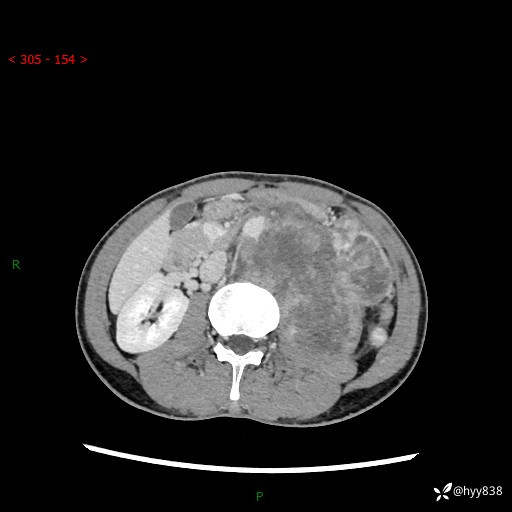

简要病史:患者无明显诱因出现左侧下腹及左侧腰背部疼痛,为间歇性隐痛,我院行胃肠镜检查,提示慢性非萎缩性胃炎,予以口服药物治疗,效果欠佳,后仍觉腹痛不适,遂至当地中医医院就诊,行彩超提示左肾积水及左肾实质性占位,遂来我院泌尿外科就诊

腹部CT平扫+增强